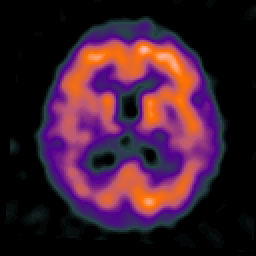

Alzheimer's disease: overlay -- Slice #15

[Home][Help][Clinical] Slice 15